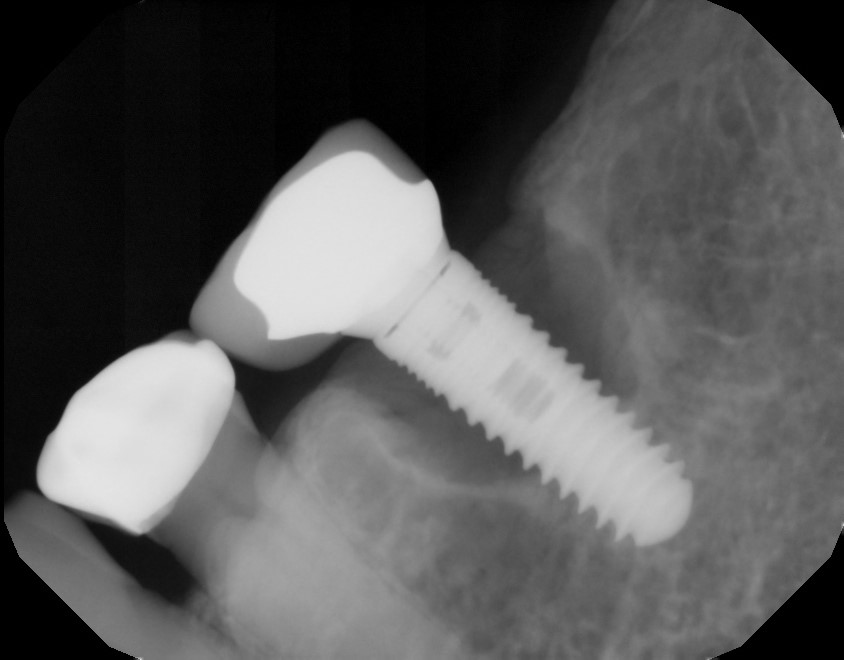

This mouth had recession on just one tooth with very little bone to support the tooth. The area needed support and thickness. The tissue was placed and the area now has thicker tissue to withstand the forces that the patient needs to place on it.